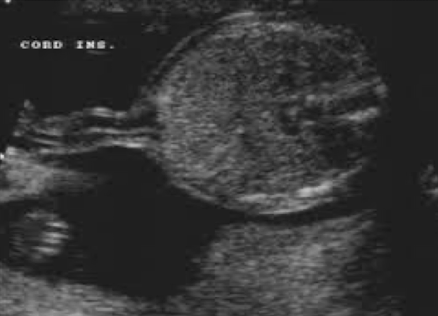

abdominal cord insertion (ACI)

becomes belly button after born

umbilical cord seen entering fetal abdomen just above level of bladder

UV courses to liver within falciform ligament

UAs course on either side of bladder

2VC can cause IUGR or is an indication of chromosomal abnormality

SONO:

image ACI with and without color Doppler

ensure smooth abdominal cord insertion (should be nothing “pooching” out)

rule out gastroschisis and omphalocele